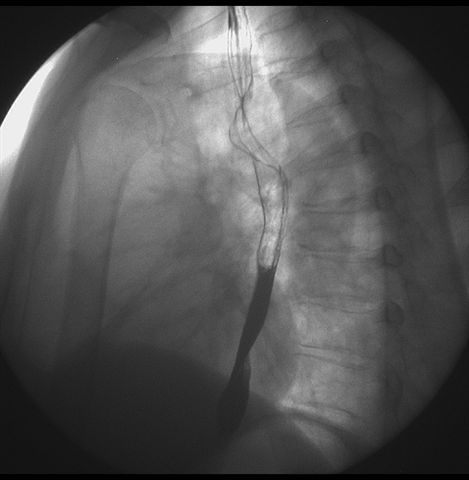

标题: X6872:F,69y,胃部不适。

胃窦至幽门段胃壁僵硬,扩张受限,局部纠集粘破坏,呈杵状。提示溃疡癌变可能性大。

支持考虑胃窦癌可能,胃内滞留液太多,胃窦部僵硬。

瀑布型胃,胃粘膜那是一个乱,窦部充盈不好,第16幅窦部粘膜反倒又很顺,先定个胃炎胃窦炎胃窦癌待排之类,建议进一步作胃镜检查。

北京肿瘤医院胃镜诊断皮革胃。